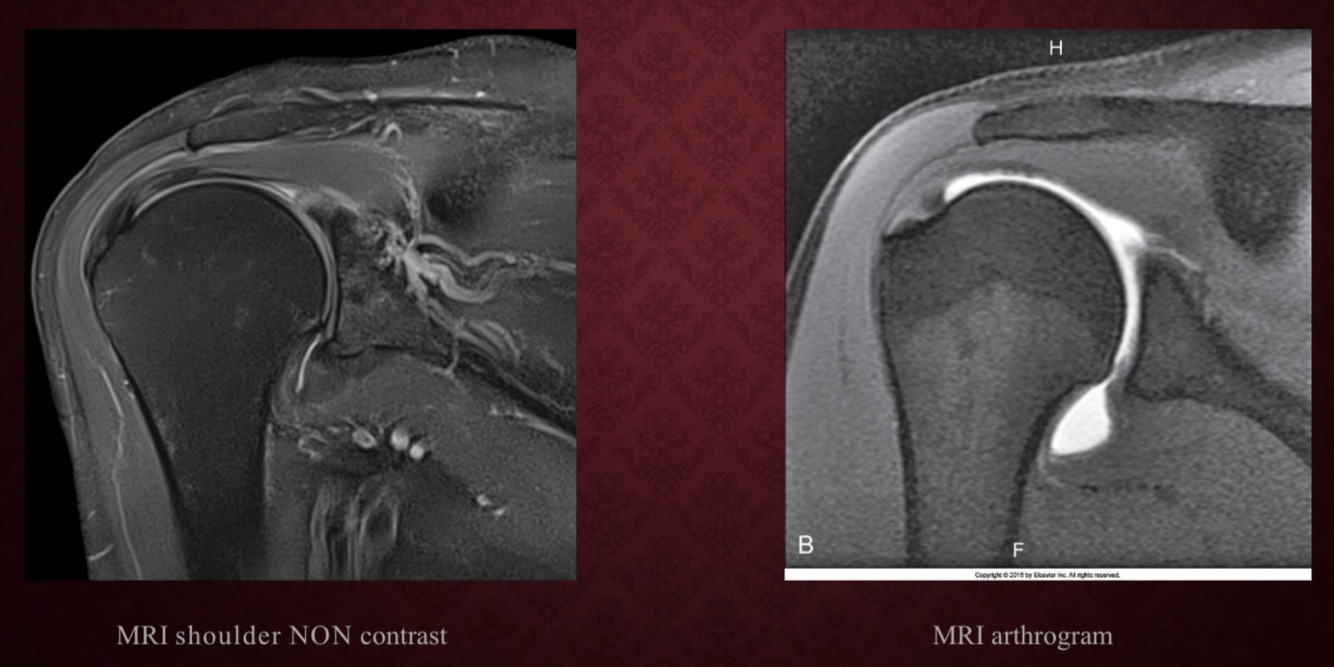

MRI Arthrogram

ARTHROGRAPHY exam commonly performed in conjunction with MRI or CT

• Demonstrates soft tissue structures within the joint capsule (ie: meniscus, ligaments, articular cartilage, and bursae)